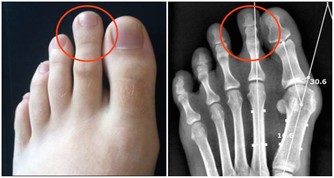

❶ 痛點能觸摸到

想減少腰病的風險,試試做這些吧

腰部肌肉和筋膜位置較淺,一旦疼痛,容易觸摸到痛點,因此,這類疼痛多半是我們熟知的腰肌勞損。